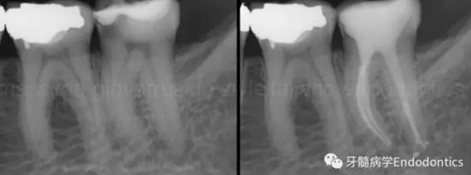

圖1.探查冠方2/3可以獲得有關(guān)根管系統(tǒng)解剖形態(tài)的相關(guān)信息,獲得根管彎曲和多重彎曲程度,或者是否存在根管彎曲的一些重要反饋。醫(yī)生需要重視五種可能遇到的根管解剖類型(包括融合、彎曲、多重彎曲、分歧、分支)。

當(dāng)建立直線通路、找到所有的根管口后,重心應(yīng)轉(zhuǎn)移到根管預(yù)備上。若牙髓存在活力且持續(xù)滲血,應(yīng)使髓室內(nèi)充滿粘性螯合劑。在牙髓已壞死的情況下,應(yīng)使用加熱的5.25%次氯酸鈉溶液沖洗并徹底充滿髓室。探查前,根據(jù)術(shù)前X線片測(cè)量并預(yù)彎小的不銹鋼銼,以順應(yīng)預(yù)估的根管長(zhǎng)度及彎曲度。使用0.02錐度的10號(hào)不銹鋼手用K銼探查根管冠方2/3。

圖2.疏通根管冠方2/3后,使用次氯酸鈉溶液沖洗根管,且可以使用手用器械、GG鉆(刷洗動(dòng)作)、旋轉(zhuǎn)鎳鈦成形銼預(yù)敞根管。當(dāng)冠方2/3進(jìn)行了合適的預(yù)備且充滿沖洗液后,接著進(jìn)行根尖1/3的探查以收集信息。使用小的手用銼(8號(hào)或10號(hào)K銼)疏通根管的剩余部分,確認(rèn)建立了流暢的、無阻礙的、平滑的到達(dá)根尖止點(diǎn)的引導(dǎo)通道。